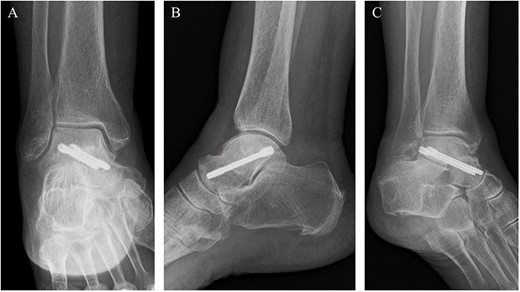

Post-operative plain radiographs revealed that two cannulated 4.5-mm double-threaded screws were inserted from the posterior part of the talus to the talar head as seen from the (A) anteroposterior, (B) lateral and (C) oblique views.